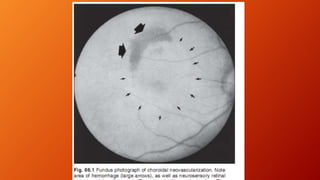

Neovascular AMD

• The hallmark of the neovascular form of AMD is the

presence of CNV. Degenerative changes in the Bruch

membrane—such as the accumulation of drusen and the

progressive thickening of membrane’s inner aspect that

characterize nonneovascular form of AMD—can be

associated with a proangiogenic environment, including

neovascularization that originates from the

choriocapillaris and perforates the outer aspect of the

Bruch membrane. These new vessels are accompanied by

fibroblasts, resulting in a fibrovascular complex that can

leak and bleed and may disrupt and destroy the normal

architecture of the RPE–photoreceptor complex,

ultimately leading to the formation of a hypertrophic

fibrotic disciform scar.